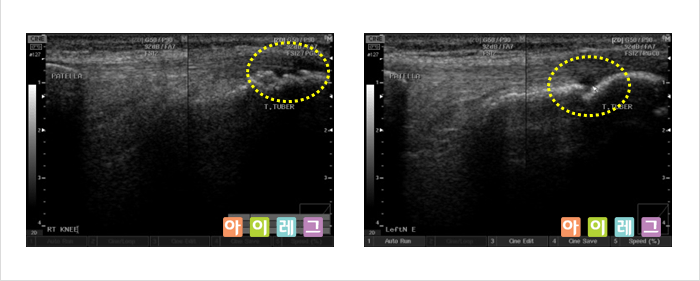

근골격계 초음파는 비전리 방사선의 한 종류인 초음파를 이용하여 영상을 만들어 냅니다. 초음파는

환자에 미치는 통증이나 방사선 노출이 전혀 없는 안전한 검사방법으로 관절,

연골, 인대, 건(힘줄), 점액낭, 근육, 신경 등 우리 몸을 움직이는 근골격계 구조물들의

이상(물이 차거나 염증 혹은 손상이 생긴 경우)을 진단하는 검사입니다. 환자의 진찰과

동시에 간편하게 시행할 수 있고, X-ray 등 방사선

검사로서 확인할 수 없는 경우 진단이나 치료에 도움이 됩니다.

또한, 근관절 정밀영상에 이용되는 고가의 MRI(자기공명영상)검사에 비해

저렴한 비용으로 시행할 수 있다는 장점이 있습니다.

* 위 영상은 모두 아이레그 의원에서 직접 검사한 영상 입니다.